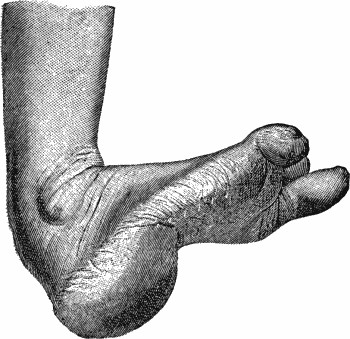

Fig. 1.—Multiple Fracture of both Bones of Leg.

A bone may be broken at several places, constituting a multiple fracture (Fig. 1).